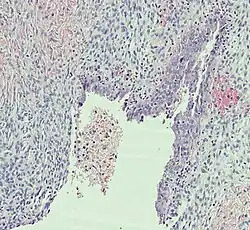

Histopathology

In case an ovarian cyst is surgically removed, a more definite diagnosis can be made by histopathology:

Type Subtype Typical microscopy findings Image

Endometriosis At least two of the following three criteria:[28]

Borderline tumor Atypical epithelial proliferation without stromal invasion.[29]